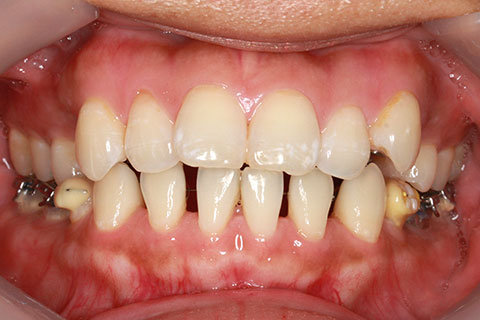

ハーフリンガル矯正3:上の歯のみ舌側矯正で治療(矯正期間24ヶ月)

治療前

治療中(開始直後)

治療中(開始半年後)

治療後

- 年齢・性別

- 25歳女性

- 治療期間

- 2年0ヶ月

- 抜歯

- 上下4番抜歯

- 治療費

- 110万円

- 治療内容

- 施術の副作用(リスク)

- 表側矯正と比較して、力学的な操作性が複雑なため、ボーイングエフェクトを起こしやすい。